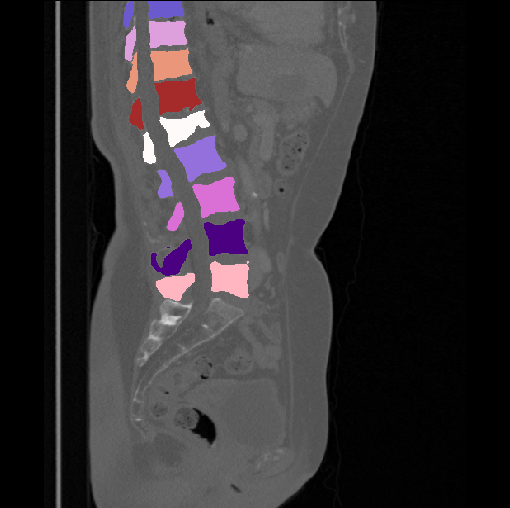

Images

GT

Predictions

We calculate the two metrics of each vertebra, and the results are reported in Table 2. On the one hand, our experimental results are close to those reported in reference (Sekuboyina et al., 2020) with the same model (nnUnet), verifying the high quality of our annotations. On the other hand, Table 2 shows it is difficult to segment the diseased vertebrae (the DSC of L6 is almost 0). Specifically, the existence of L6 confuses the model, resulting in prediction dislocations (see the last row in Fig. 4). Thus, our labeled dataset, which contains many L6 cases, is very valuable for the diseased vertebrae segmentation (we have stated those cases that are hard for annotation in the readme.txt file). Table 2 illustrates that the model trained with our annotations can achieve good performance on our CTSpine1K dataset but a much worse performance on the VerSe Challenge datasets, which explains there is an obvious domain gap between our annotated dataset and the public dataset. We infer the reason is that the COlONOG dataset is based on an empty stomach and colon, confusing the deep learning model by the changes of air content in the abdomen (see Fig. 3). Therefore, our annotations are a good complement to the existing datasets.

3.2.2 Qualitative results.

Some visualization results are presented in Fig. 4, where we can observe that the baseline model can achieve excellent segmentation results. Nevertheless, some failed predictions occur when spinal diseases exist, especially sacral lumbarization and lumbar sacralization. Besides, the image’s resolution of Z direction is closely related to the results, and a lower resolution leads to worse results. Maintaining a reasonable performance for a low resolution is a research challenge. Image superresolution (Peng et al., 2020) might be worth exploring.